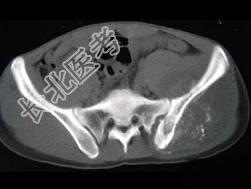

- 单项选择题男,35岁, 左髂部剧烈疼痛,尤以夜间明显, 可摸到肿物,结合图像, 最可能的诊断是 ( )

A、骨巨细胞瘤

B、软骨肉瘤

C、骨转移瘤

D、骨肉瘤

E、软骨瘤